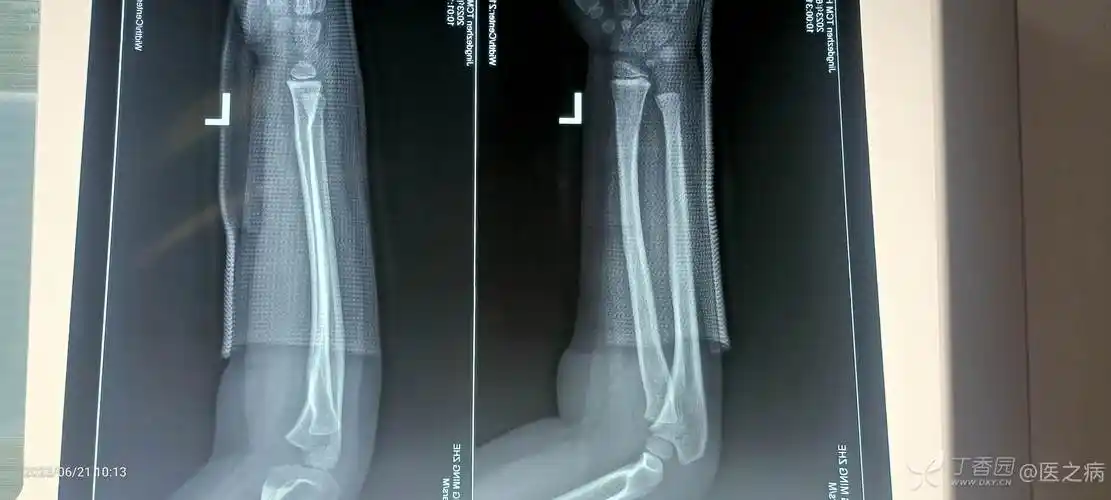

三周岁宝宝小腿胫骨青枝骨折,到医院医生没有复位直接打了石膏,但一个

9岁小孩左小腿胫骨中下段青枝骨折要不要固定,谢谢了